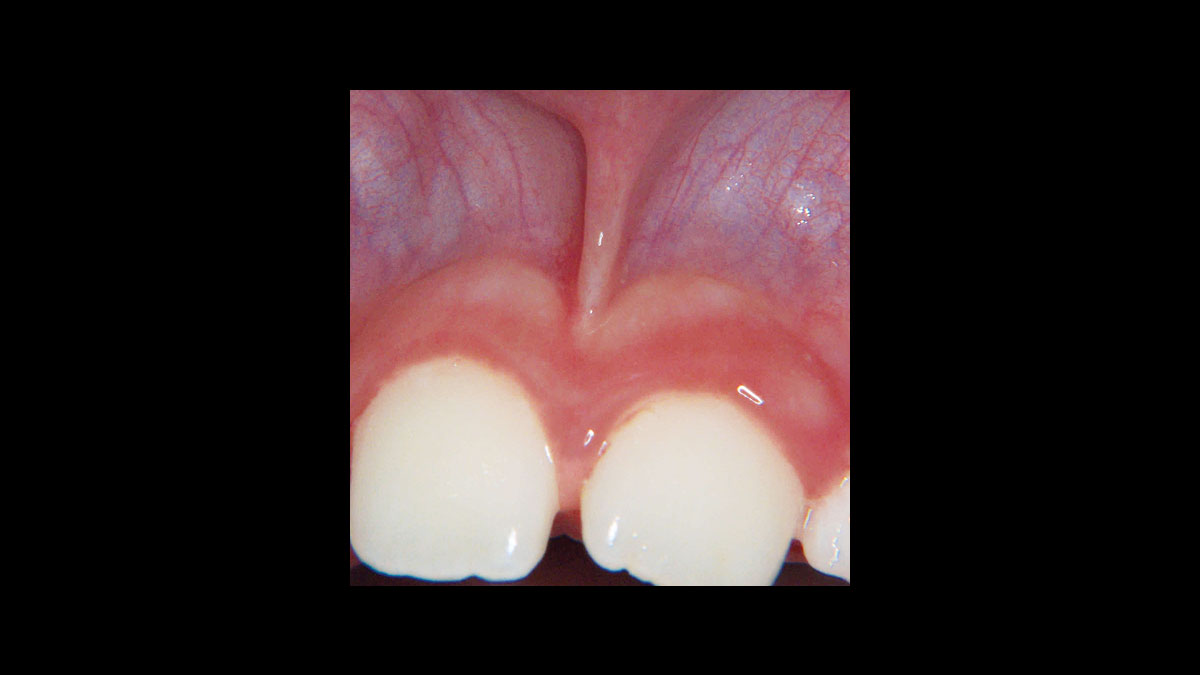

• Frenectomía

Frenectomía